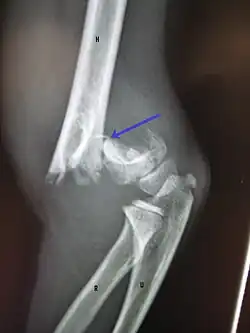

A fracture of the greater tuberosity as seen on AP X ray -

A fracture of the greater tuberosity of the humerus -

Fracture of the greater tuberosity of the humerus -